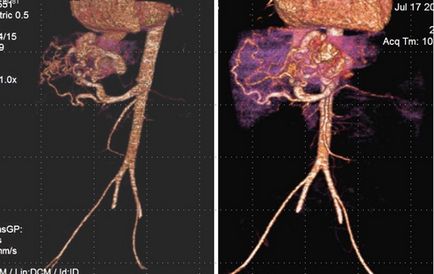

A fost detectată o șuntură arterio-venoasă între ramura arterei hepatice comune și vena cavă inferioară.

După 2 luni pe fondul tratamentului cu propranolol, structura educației sa schimbat, șuntul arterio-venos a dispărut între ramura arterei hepatice comune și cea inferioară a venei cava.

Caracter dinamic schimbare structurii neoplasmul sub forma reducerii diametrului vaselor de sânge și dispariția șunt arterio-venos, împotriva tratamentului conservator a ajutat confirma diagnosticul „congenital (infantil) ficat hemangiom.“